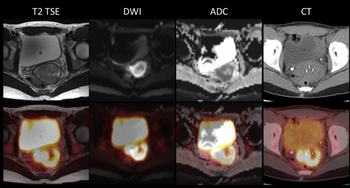

Could PET/MR be a better modality than conventional MR and CT for bladder cancer?

Washington University’s Mallinckrodt Institute of Radiology is imaging cervical cancer patients with hybrid PET/MR. Here’s what they’ve learned about this new modality.